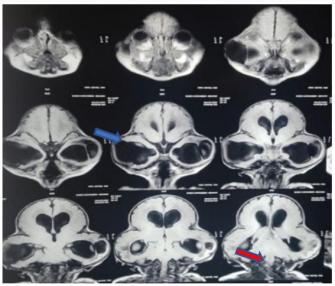

3D 磁共振图像显示双侧冠状缝、菱形缝和矢状缝过早融合

T2 冠状位图像显示代偿性脑积水(蓝色箭头)和 Arnold Chiari I 畸形(红色箭头)

图4、5:来源于文献[5]